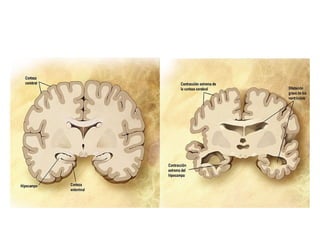

• TC de Crânio: Inespecífica: Atrofia cortical, aumento

de sulcos, lesões vasculares maiores.

• RNM de Crânio: Visualiza bem hipocampos,

substância branca e cinzenta, lesões vasculares

menores, delimita melhor área de atrofia.

• SPECT: Hipofluxo parietal ou parietotemporal

• PET: com PIB, Pittsburgh compound B

• Liquor: Proteína Tau, fosfotau, csf e betaamilóide.

• Novidade: Exame de retina em betaamilóide